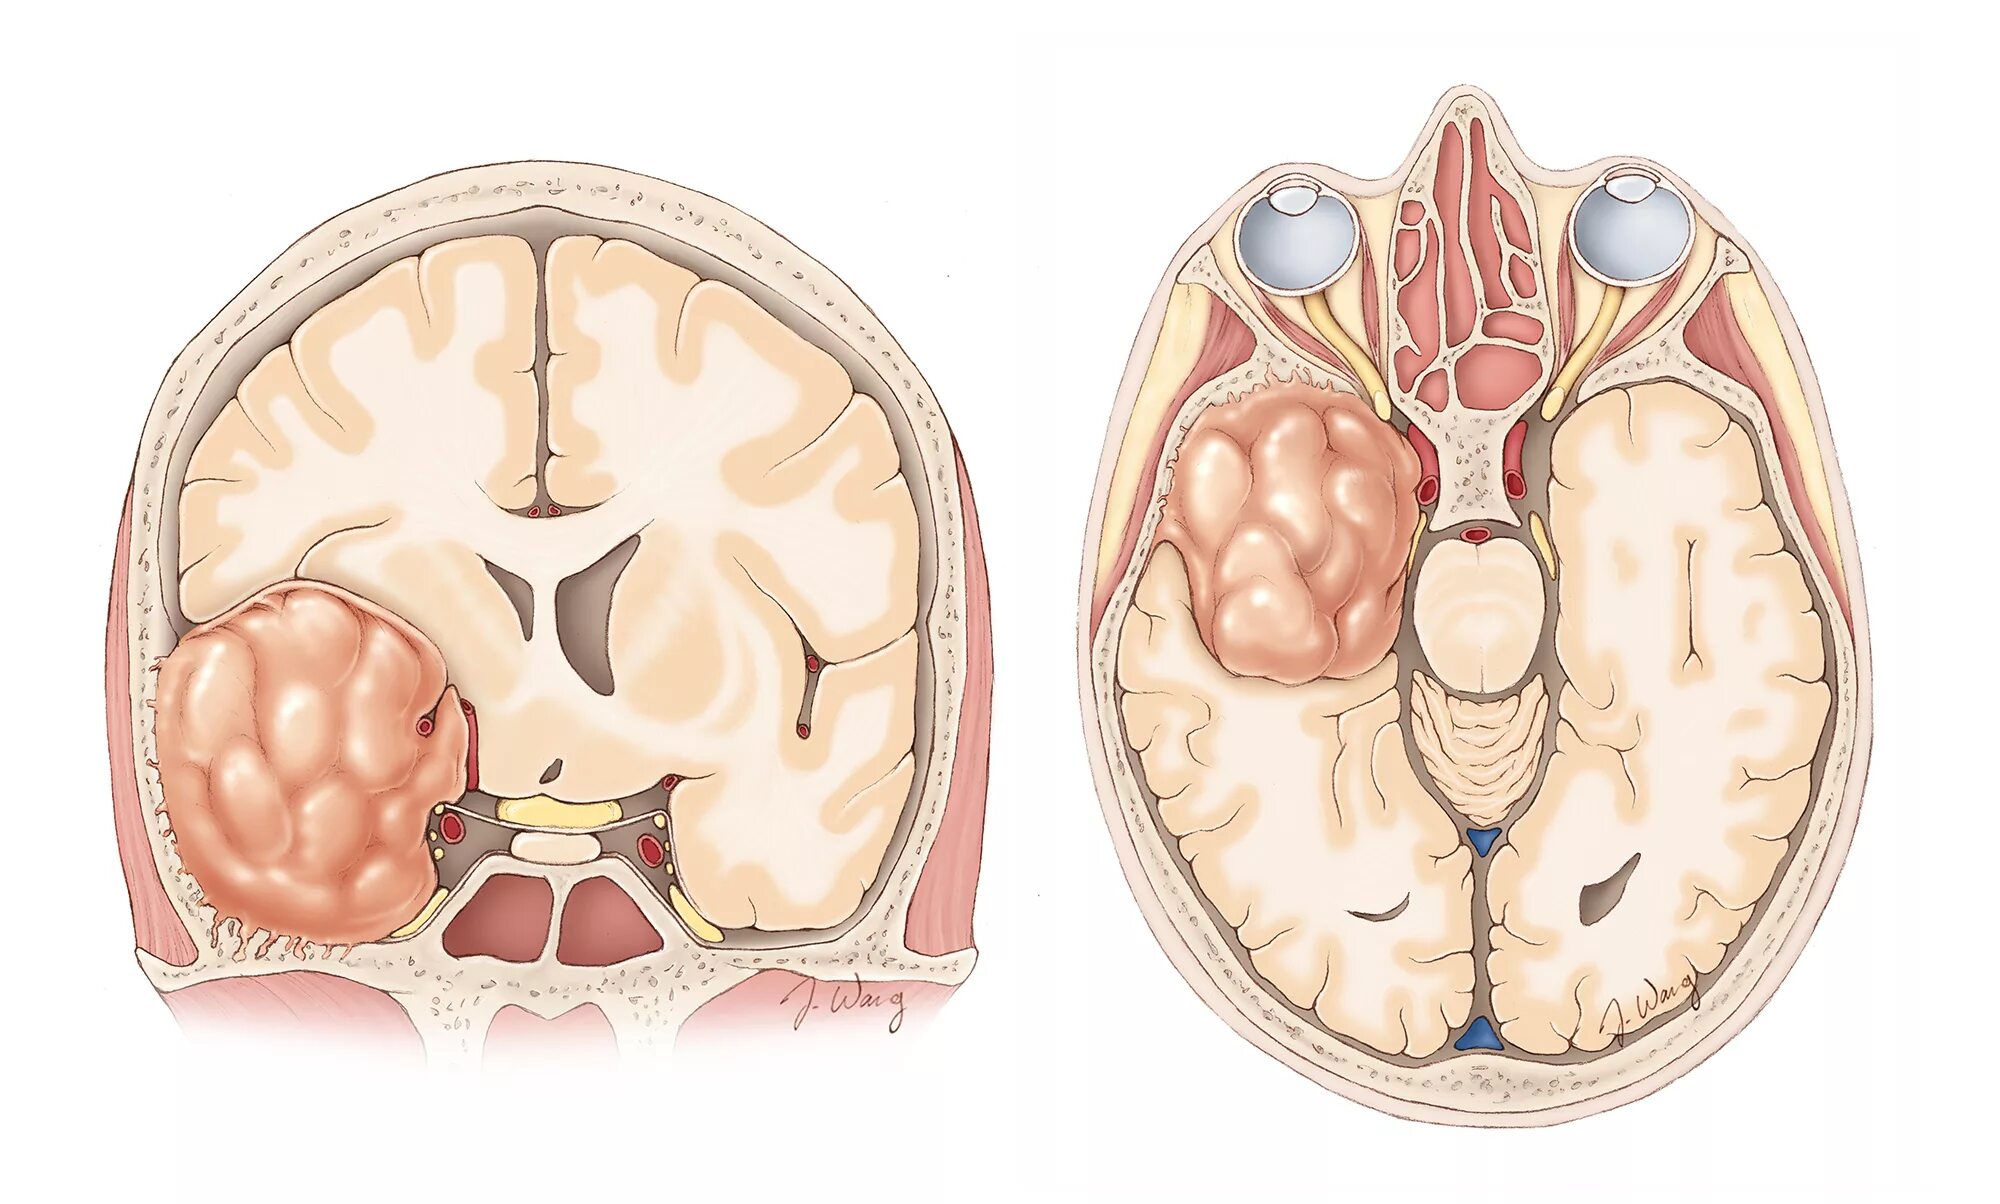

Базальная опухоль